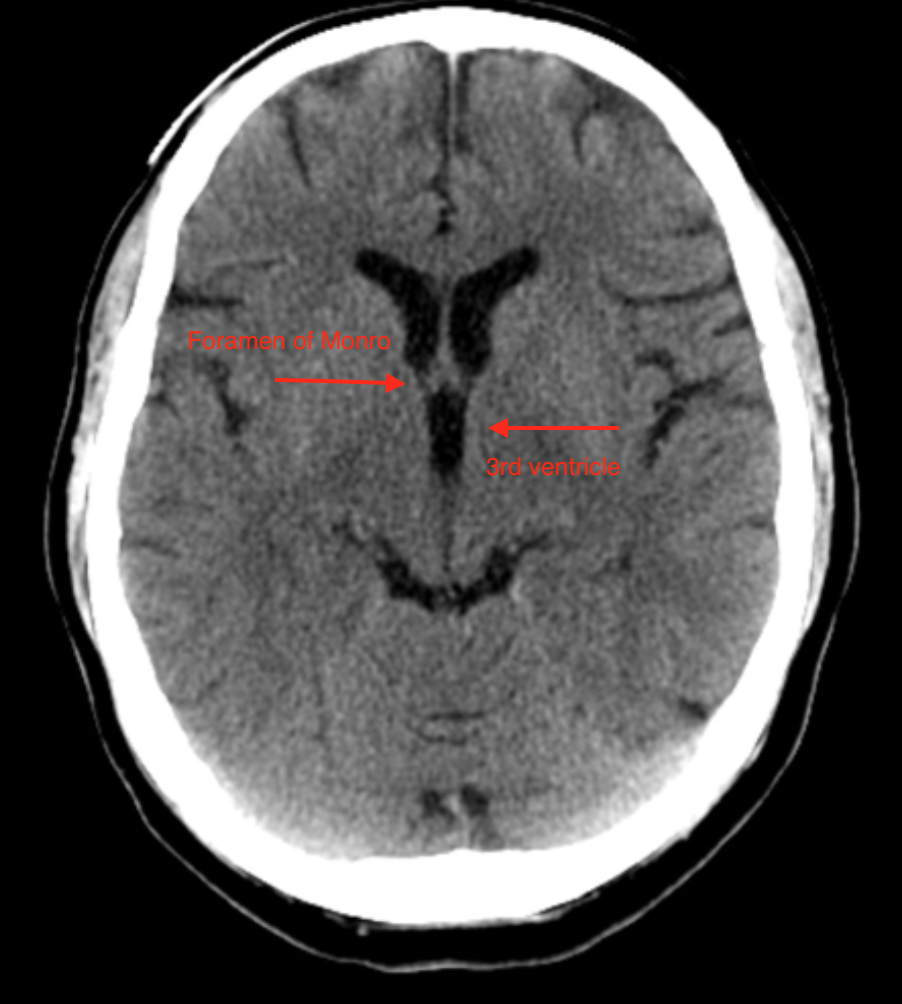

Ventricles & Cisterns:

• Lateral ventricles —> Foramen of Monro —> 3rd ventricle —> cerebral aqueduct —> 4th ventricle —> foramen of lushka —>cerebellopontine cistern